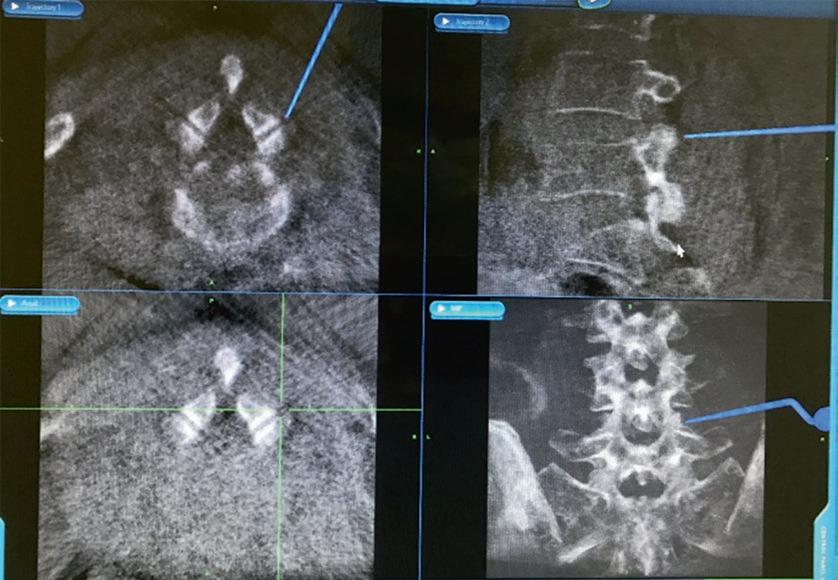

计算机辅助脊柱手术(CASS)是一门使用新的基于计算机的技术的学科,包括立体定向、导航手术和机器人技术。导航辅助脊柱手术是一组技术,它允许外科医生在手术中获取与手术器械相关的实时、三维和虚拟的脊柱图像。